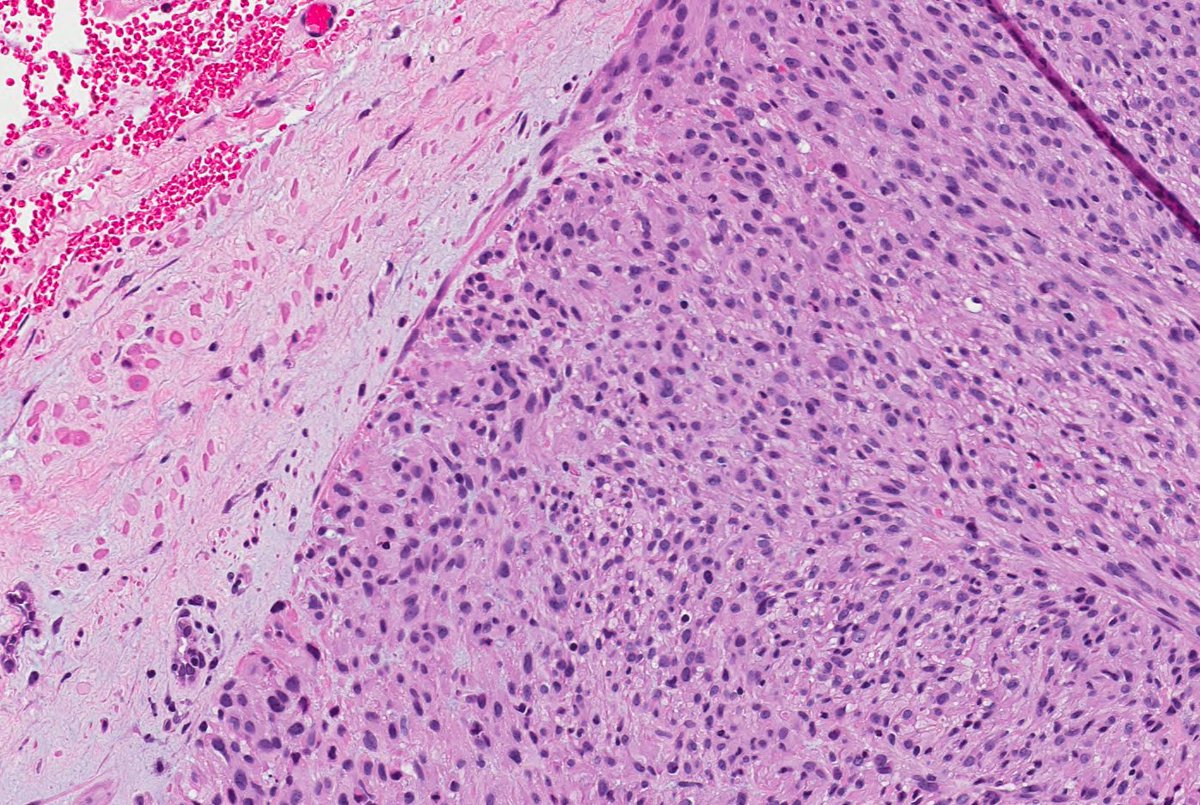

Remember leiomyosarcomas arising from vessels may be aggressive unlike leiomyosarcoma from arrector pili. This LMS arising from vein; note residual vascular wall at periphery. Residual vein top left corner on image 2 & 3. Ref: Italiano A, et al. PubMed PMID: 20167595. #dermpath